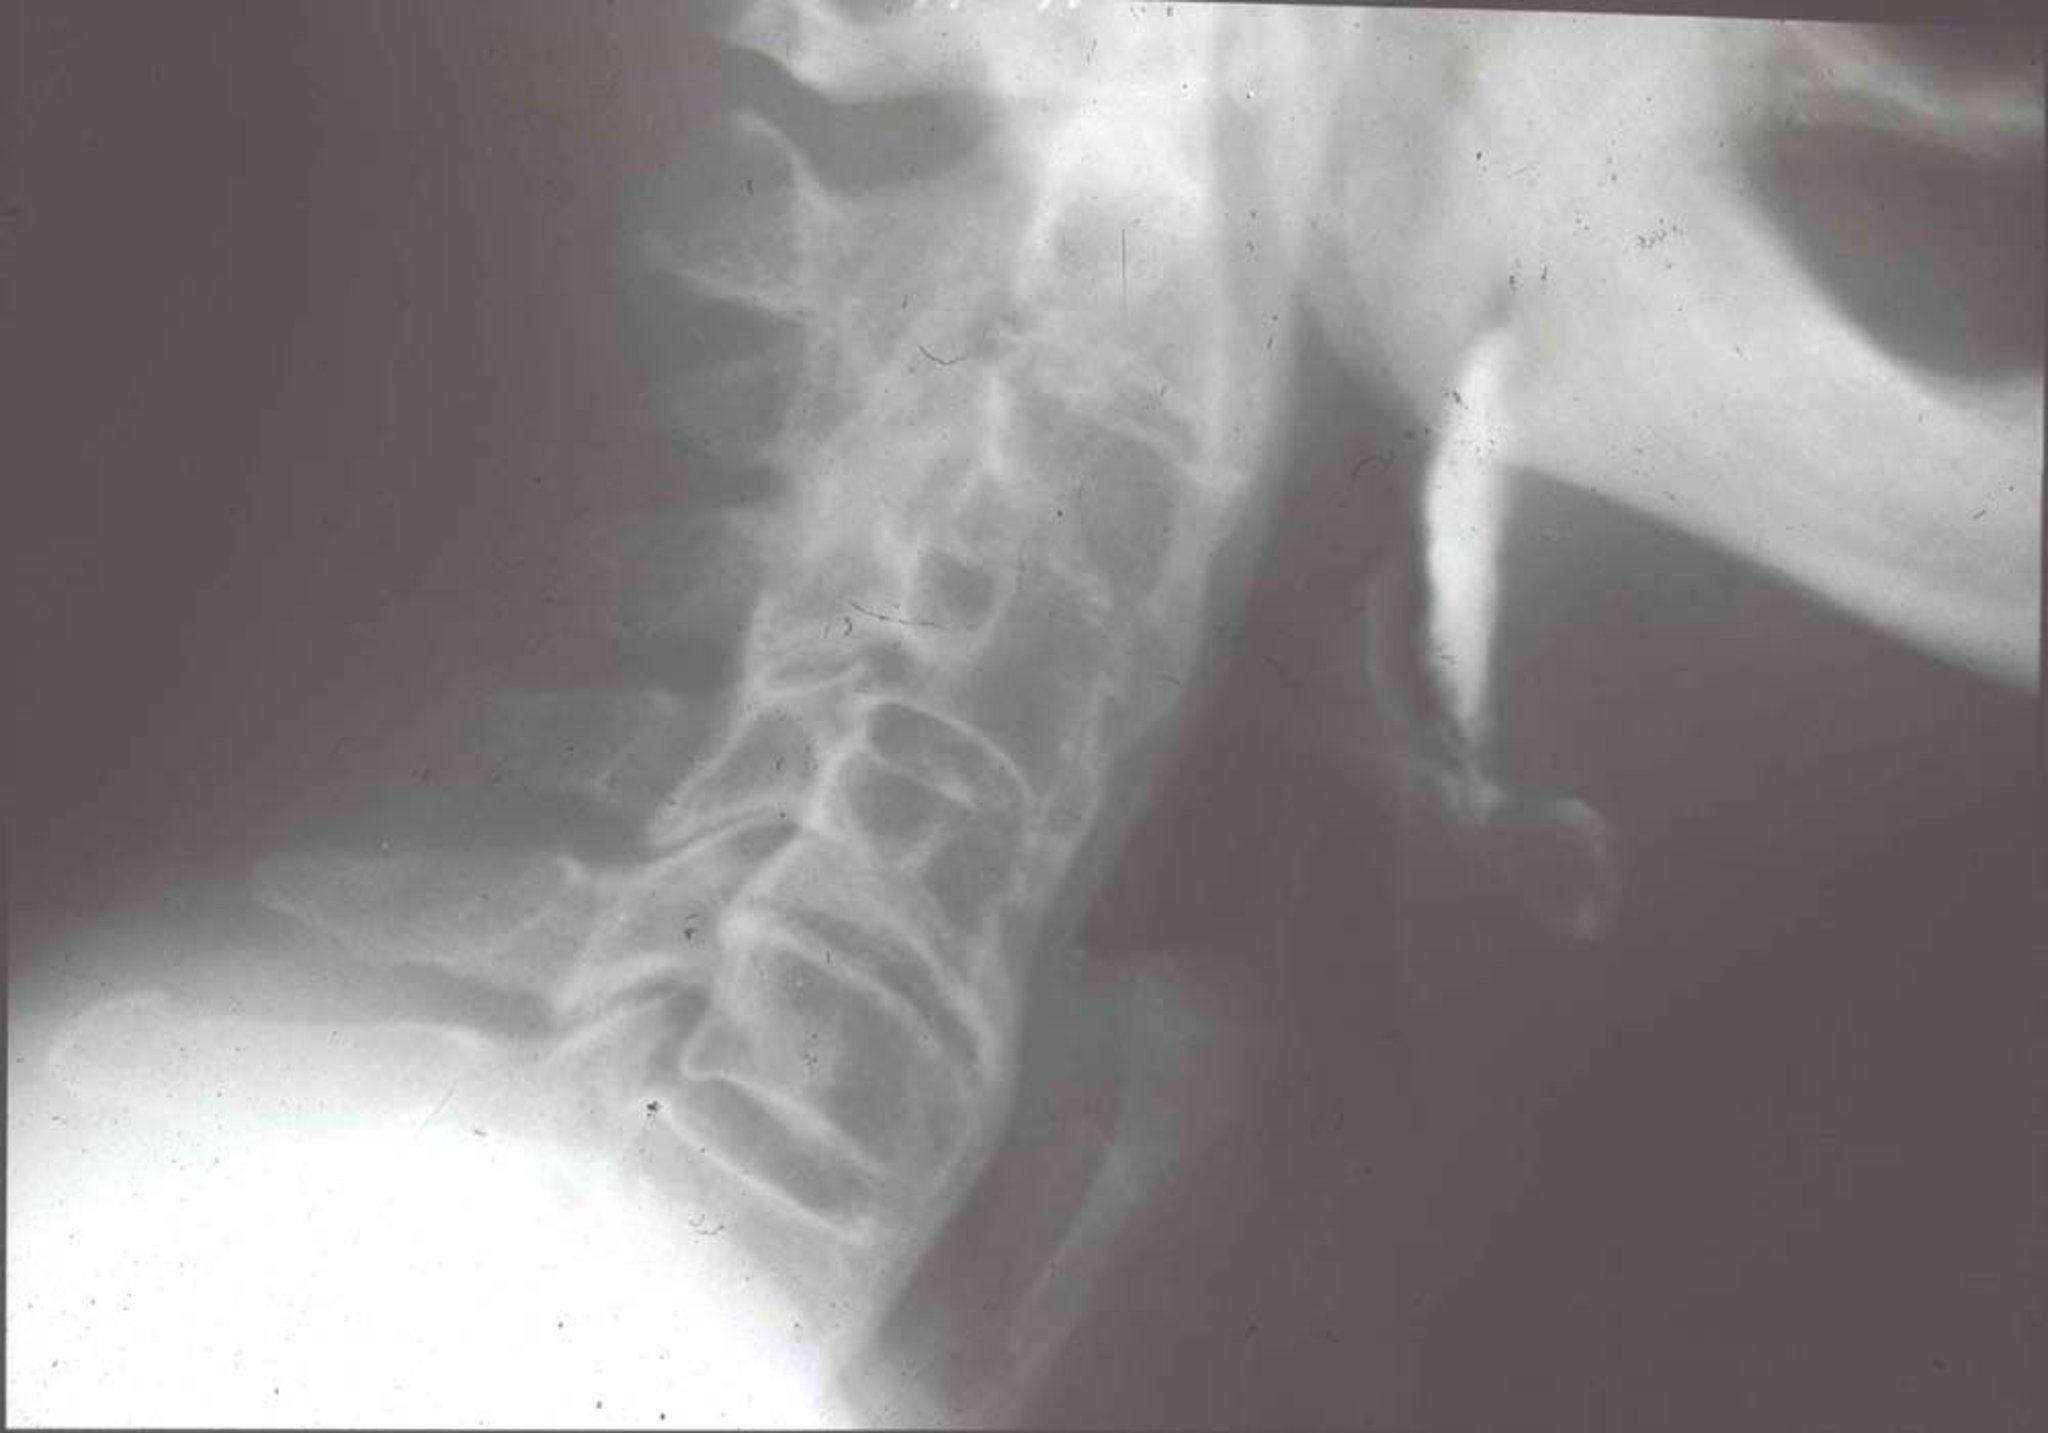

Hiperostose esquelética idiopática difusa (Radiografia)

As alterações radiológicas características incluem grandes ossificações anteriores aos corpos vertebrais (a calcificação parece como se alguém tivesse derramado cera de vela na frente e nos lados das vértebras), ligando várias vértebras.

Imagem fornecida por Roy Altman, MD.